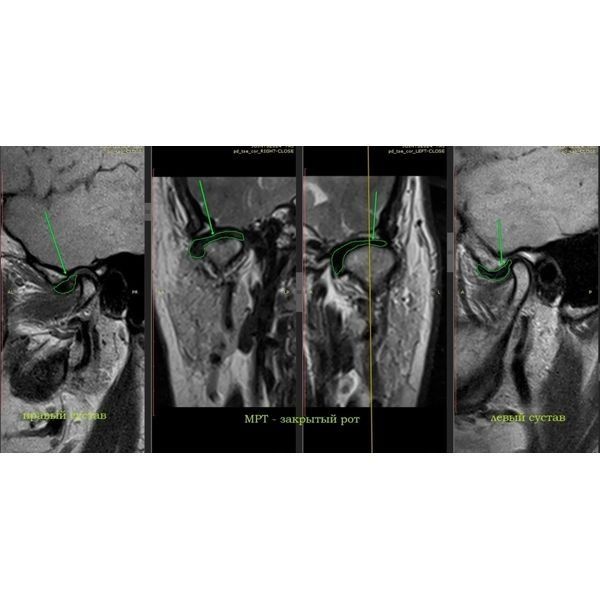

По результатам магнитно-резонансной томографии (МРТ) правого сустава:

- полное вентральное смещение суставного диска с редукцией — диск смещён вперёд, но при открытии рта суставная головка «запрыгивает» на диск;

- дистрофические изменения диска — диск начал терять эластичность и нормальную структуру;

- тенденция к перфорации промежуточной зоны диска — в средней части диска появляется риск возникновения сквозного отверстия;

- дорзальный тип установки головки мыщелкового отростка нижней челюсти — головка нижней челюсти стоит слишком далеко назад (дорзально) в суставной ямке (неправильное положение);

- остеоартроз ВНЧС 2-й степени по Kellgren — начальные дегенеративные изменения сустава.

МРТ левого сустава выявила:

- вентромедиальное смещение суставного диска с частичной редукцией — диск смещён вперёд и немного внутрь (медиально), при открывании рта он частично возвращается на место;

- компрессионный тип установки головки мыщелкового отростка — головка нижней челюсти сильно прижата к суставной ямке;

- гипермобильность головок суставных отростков — головки нижней челюсти избыточно подвижны;

- дистрофические изменения диска;

- остеоартроз ВНЧС 1-й степени по Kellgren.